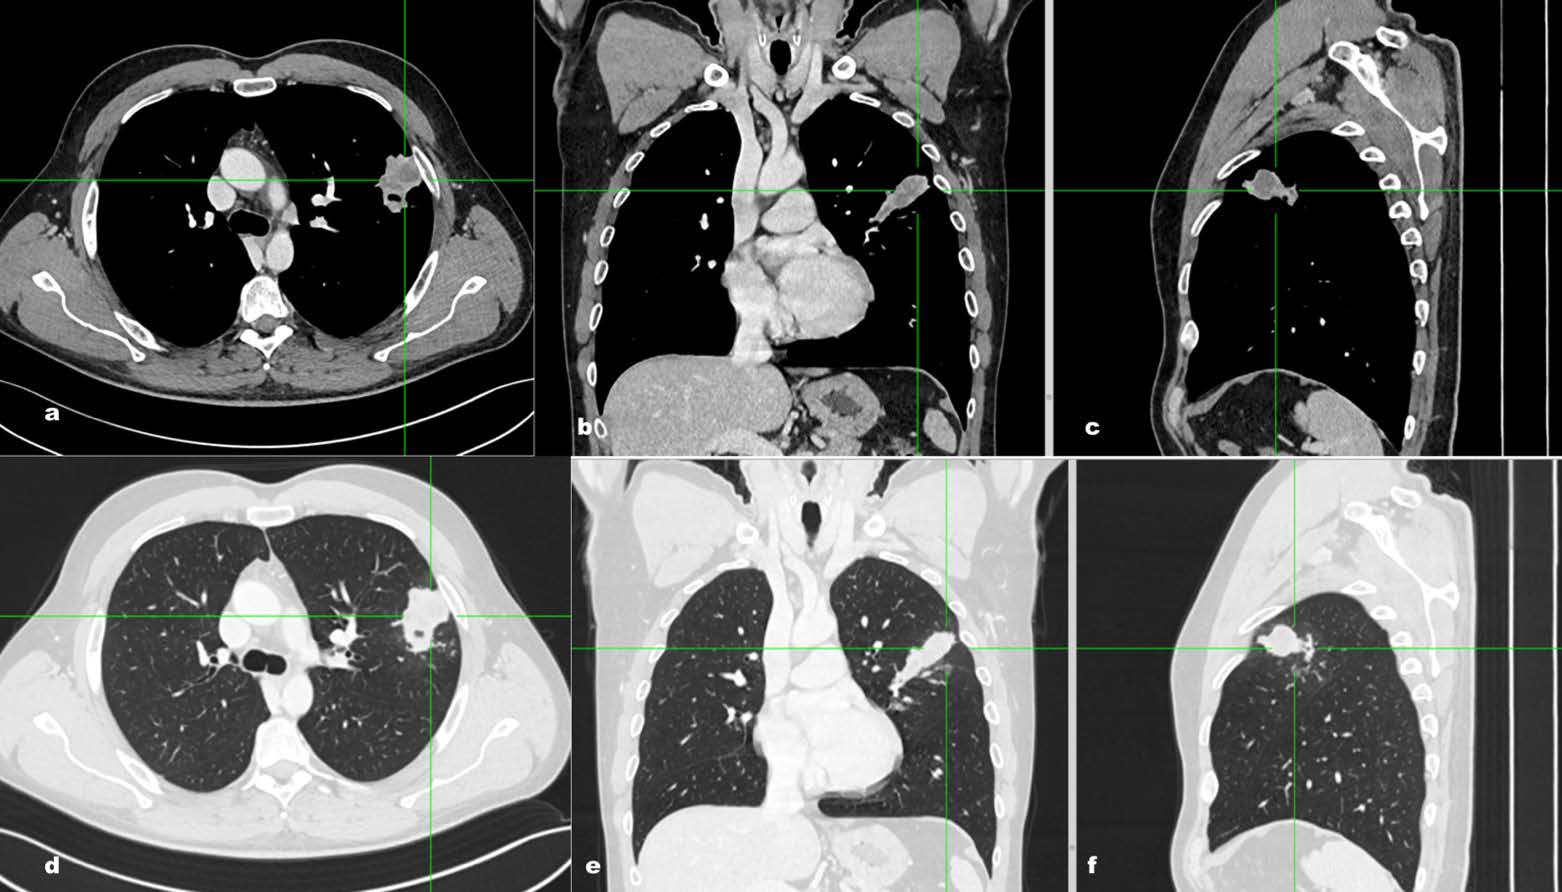

An Eosinophilic Pneumonia Mimicking Lung Cancer on Multiple Imaging Modalities Monitored By CT

Filippo Montella, Ghassan Merkabaoui, Antonietta Vitale, Guido Faggian, Serena De Luca

1-9

PDF